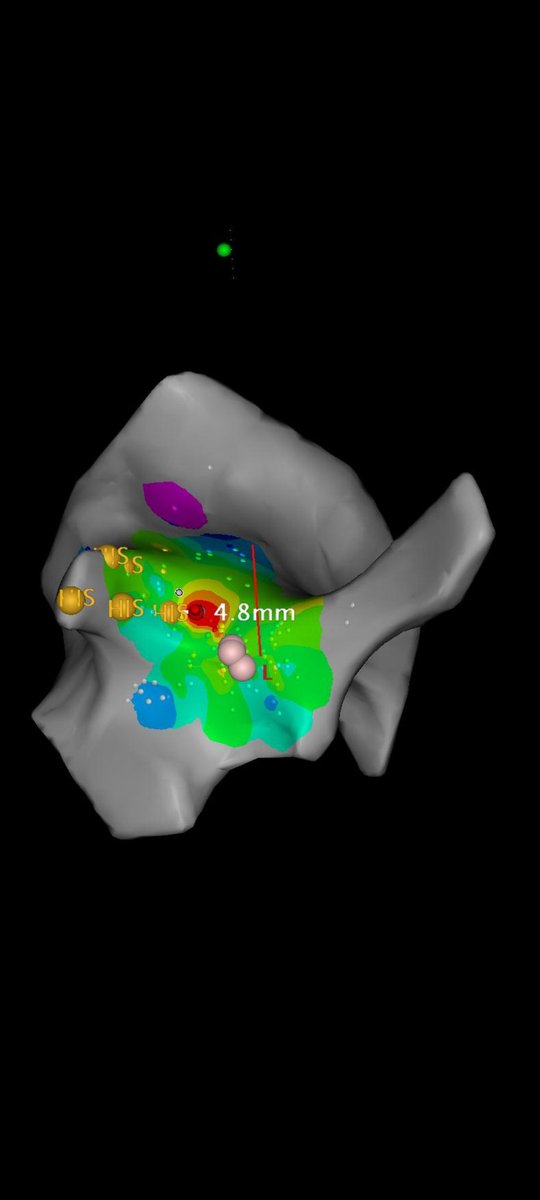

Almost incessant JET alternating with bigeminated junctional premature beats (most of them with anterograde block). Mapped during JET. Yellow dots=His area. Red area: earliest atrial activation. Succesfully ablated 5 mm away from his (20W). Thanks to @AlemunozAR for the map.